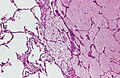

Pulmonary alveolar proteinosis. H&E stain. | |

| LM | "dense bodies" or "chatter" (represent dead macrophages) within acellular eosinophilic material that is in the alveoli |

Microscopic

Features:

- Crap in the alveoli:

- "Dense bodies" - dead macrophages ("Chatter" in the alveoli).

Sections show lung with eosinophilic material in the airspaces. Focally, small (~20 micrometres), more dense appearing, bodies are also in the airspace. The alveolar walls are within normal limits. No significant inflammation is identified. No microorganisms are seen with routine stains. There is no pulmonary hemorrhage.